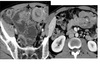

Zenker Diverticulum

Outpouching with rounded contour posteriorly in the neck is above the cricopharyngeus muscle

In hypopharynx!!!

Site of weakness is the Killian dehiscence - between the inferior pharyngeal constrictor muscle and cricopharyngeal muscle